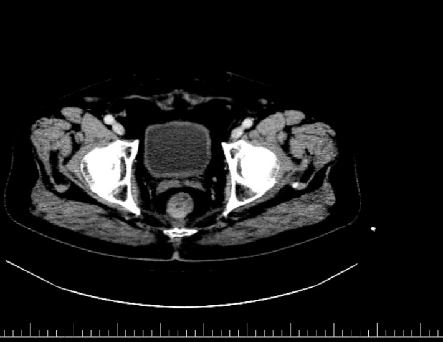

胸腹盆增强CT(2020-05-08):直肠癌治疗术后,左下腹造瘘术后,肝脏多发转移较前增多增大,双肺气肿,主动脉及冠状动脉硬化,双肾囊肿

诊断:直肠腺癌术后,转移(肝)。